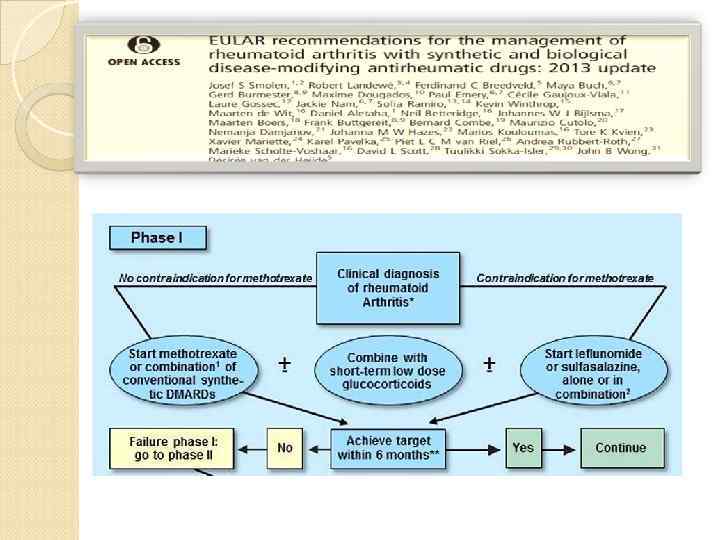

Фаза 1 Нет противопоказан к назначению Клинический метотрексата Назначение метотрексата Переход Ко II фазе НЕТ + диагноз РА Противопоказания для метотрексата + Комбинирование с непродолжительным курсом ЛЕФЛЮНОМИД, ЗОЛОТО, СУЛЬФАСАЛАЗИН ГКС в малых или бол дозах Достижение ремиссии или низкой активности через ДА Продолжение 3 -6 мес

Фаза 1 Нет противопоказан к назначению Клинический метотрексата Назначение метотрексата Переход Ко II фазе НЕТ + диагноз РА Противопоказания для метотрексата + Комбинирование с непродолжительным курсом ЛЕФЛЮНОМИД, ЗОЛОТО, СУЛЬФАСАЛАЗИН ГКС в малых или бол дозах Достижение ремиссии или низкой активности через ДА Продолжение 3 -6 мес

Фаза 2 Прогностически неблаг факторы Недостаточный эффект или развитие побочных реакций Присоединение биолог агентов (инг ФНОά) НЕТ Переход Ко IIIфазе НЕТ Неблагоприятн факт отсутств ЛЕФЛЮНОМИД, ЗОЛОТО, СУЛЬФАСАЛАЗИН в виде монотерапии или комбинированной терапии Достижение ремиссии или низкой активности через 3 -6 мес ДА Продолжение

Фаза 2 Прогностически неблаг факторы Недостаточный эффект или развитие побочных реакций Присоединение биолог агентов (инг ФНОά) НЕТ Переход Ко IIIфазе НЕТ Неблагоприятн факт отсутств ЛЕФЛЮНОМИД, ЗОЛОТО, СУЛЬФАСАЛАЗИН в виде монотерапии или комбинированной терапии Достижение ремиссии или низкой активности через 3 -6 мес ДА Продолжение

Фаза 3 Биологические агенты + синтетические БМ Недостаточный эффект или развитие побочных реакций на 2 фазе Изменить биологическую терапию: -второй ингибитор ФНО; или Ритуксимаб Тоцилизумаб абатацепт Достижение ремиссии или низкой активности через 3 -6 мес НЕТ ДА Продолжение

Фаза 3 Биологические агенты + синтетические БМ Недостаточный эффект или развитие побочных реакций на 2 фазе Изменить биологическую терапию: -второй ингибитор ФНО; или Ритуксимаб Тоцилизумаб абатацепт Достижение ремиссии или низкой активности через 3 -6 мес НЕТ ДА Продолжение